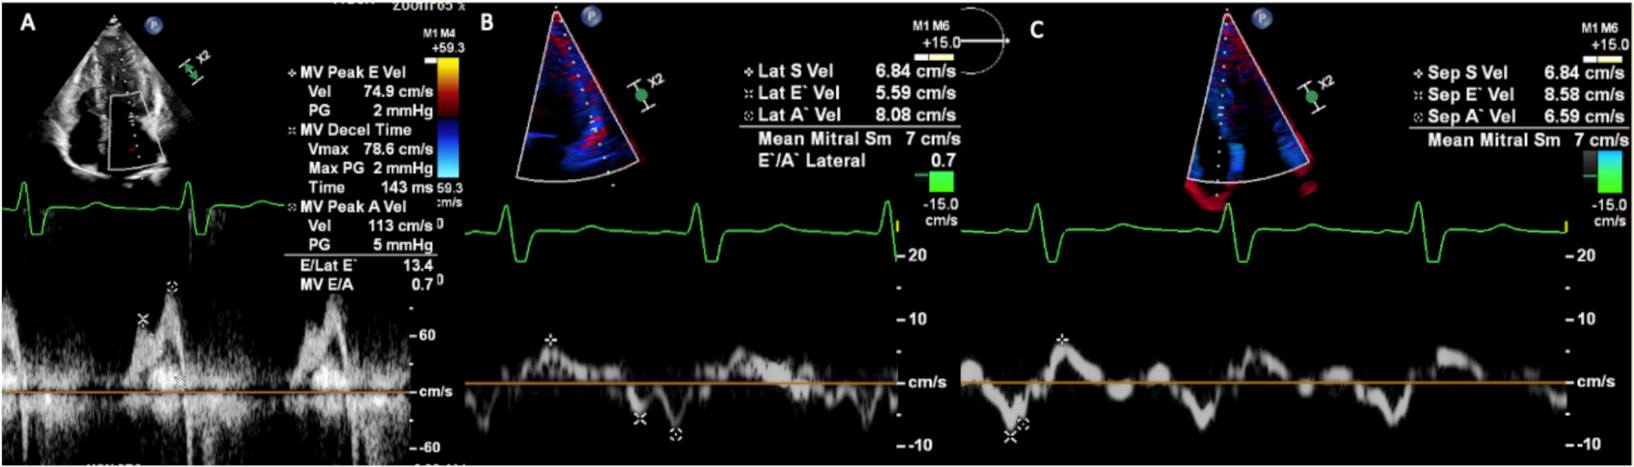

3.1. Transthoracic Echocardiography

- Impairment of TDI velocity, Doppler and speckle tracking strain and strain rate are early signs of the functional impact of sphingolipid storage on the heart;